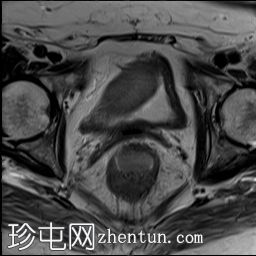

该CT扫描显示右髂血管旁有一管状结构,终止于阑尾/回盲部。

回顾患者的病史和影像学检查结果,临床和影像学特征最符合阑尾黏液囊肿的诊断。CT显示右侧半盆腔内有一边界清晰的囊性病变,大小为8.1 × 8.2 × 3.2 cm,与阑尾和右侧附件区相连。磁共振成像证实子宫和卵巢缺失,支持肿块起源于阑尾的诊断。